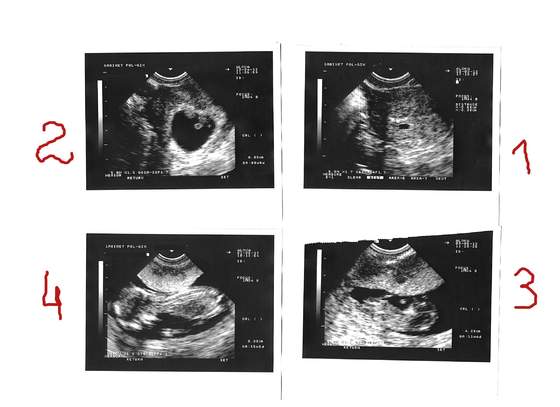

gryzoń- ja usg połówkowe mam dzień przed Tobą, czyli 23 lipca. Mam nadzieję, że poznam wtedy płeć. No i że wszystko będzie z Małym dobrze.